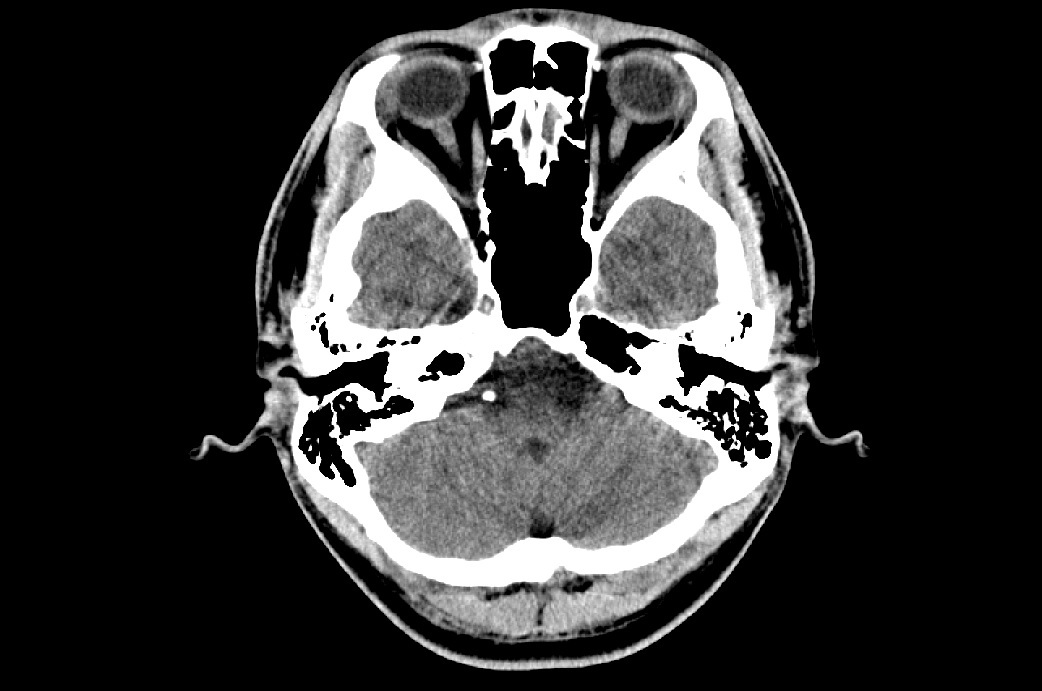

脳震盪から選手を守る